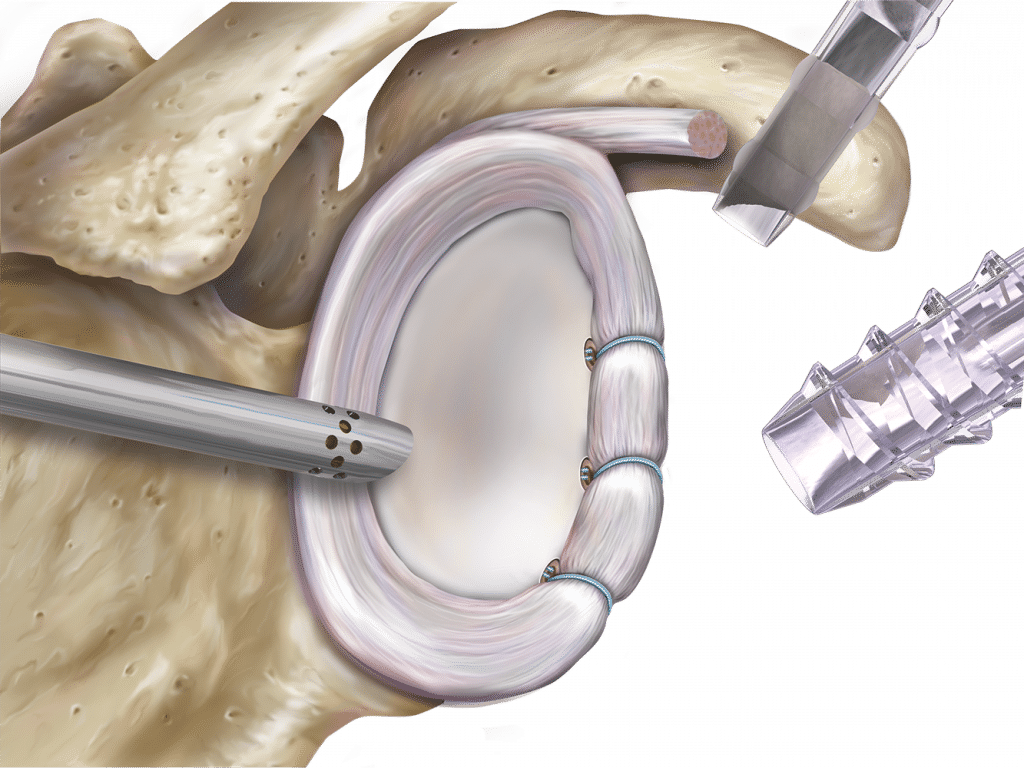

Réparation de la coiffe

L’acte chirurgical est envisagé si la rééducation ne donne pas de résultats satisfaisants. Réalisée par arthroscopie, la réparation consiste à re-fixer le tendon sur la partie supérieure de l’humérus. Cette intervention sera possible sous conditions : que le tendon ne soit pas trop rétracté, ni le muscle trop dégénéré.